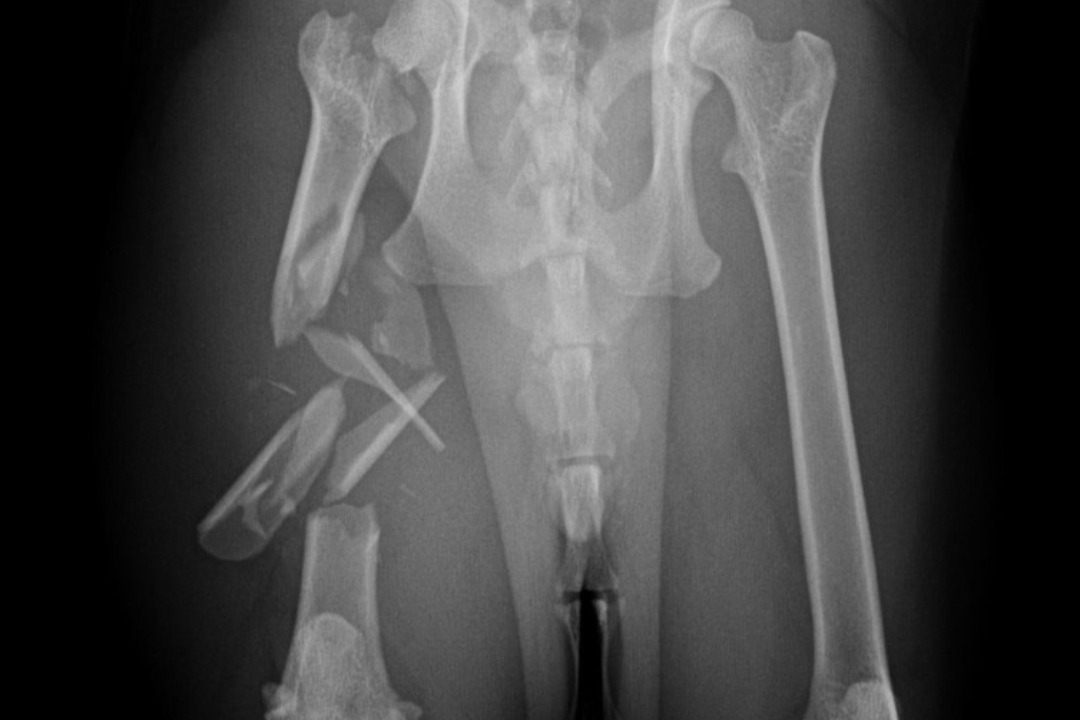

*Romeo's X-Rays*Our 4 year old cat Romeo has been SEVERELY injured and the vet stated that she believes he was crushed. When we came home after bringing him to the hospital, we realized that our boxspring was broken, so we believe that it fell onto him and crushed him. He has broken ribs, a shattered femur, etc. He will need to have his leg amputated, which in itself is $7000 and would be $17,000 if we decided to keep the leg and have them try to fix it and we genuinely cannot afford it.. And those prices are for his leg alone, it doesn't include the cost for his ribs or medications, or the $2000 a night to stay at the hospital. Please help us save our boy.. We cannot live in a world without him.. He's the most special cat in the entire world and our hearts are breaking. If we cannot afford the surgeries, then we will have to put him down. Please help in any way you can..